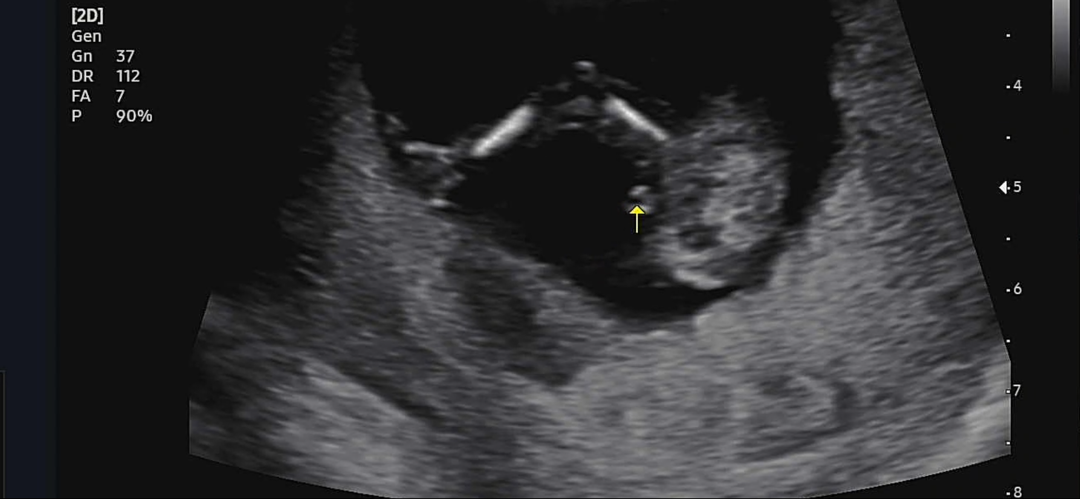

13주2일 이정도면 빼박이겠죠..?

감기기운이 심해 병원갔다왔는데 이정도면 무조건 아들이겠죠!?? 거의 변화없을거같다던데 아들맘인가봐요~!~!